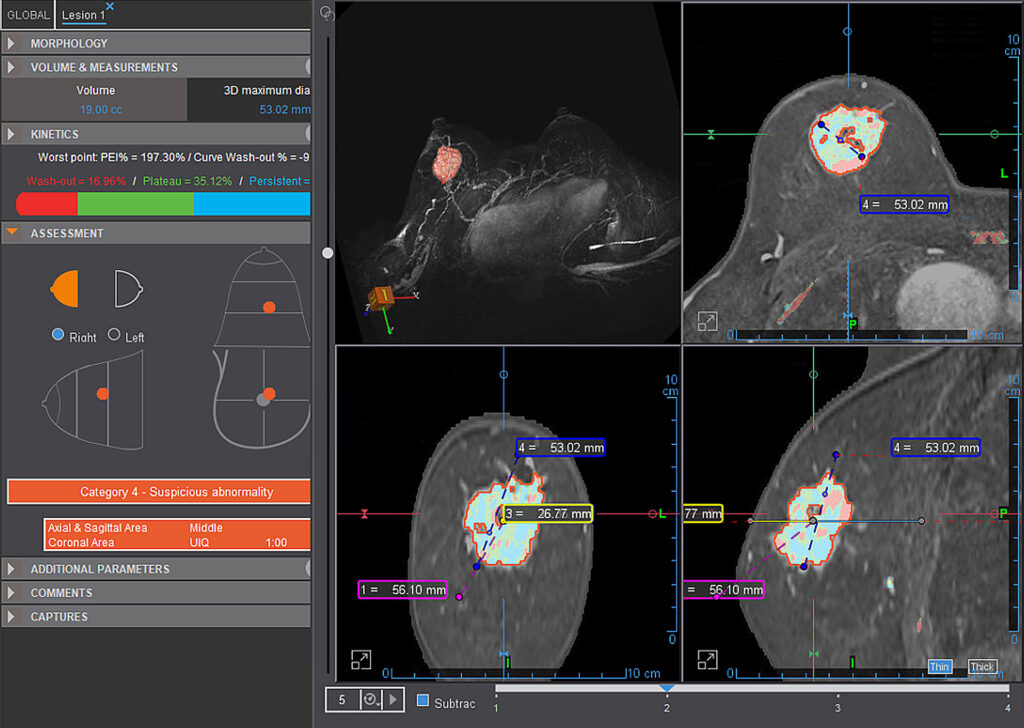

MR Breast (Basic)

Olea MR Breast applications are efficient tools for breast lesion detection, characterization and staging. Olea MR Breast applications are efficient tools for breast lesion detection, characterization and staging.

MR Breast Advanced (breastscape®)

This is a semi-automated solution for diagnostic assistance in breast lesions. Automatically computes parametric maps, segmentation of lesions and calculation of distances, lesion evolution follow-up, preparation of BI-RADS® Atlas.